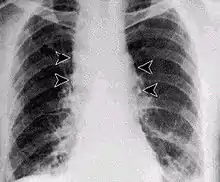

Inhalation anthrax usually develops within a week after exposure, but may take up to 2 months. During the first few days of illness, most people have fever, chills, and fatigue. These symptoms may be accompanied by cough, shortness of breath, chest pain, and nausea or vomiting, making inhalation anthrax difficult to distinguish from influenza and community-acquired pneumonia. This is often described as the prodromal period.[27]

Over the next day or so, shortness of breath, cough, and chest pain become more common, and complaints not involving the chest such as nausea, vomiting, altered mental status, sweats, and headache develop in one-third or more of people. Upper respiratory tract symptoms occur in only a quarter of people, and muscle pains are rare. Altered mental status or shortness of breath generally brings people to healthcare and marks the fulminant phase of illness.

It infects the lymph nodes in the chest first, rather than the lungs themselves, a condition called hemorrhagic mediastinitis, causing bloody fluid to accumulate in the chest cavity, thereby causing shortness of breath. The second (pneumonia) stage occurs when the infection spreads from the lymph nodes to the lungs. Symptoms of the second stage develop suddenly within hours or days after the first stage. Symptoms include high fever, extreme shortness of breath, shock, and rapid death within 48 hours in fatal cases.[28]